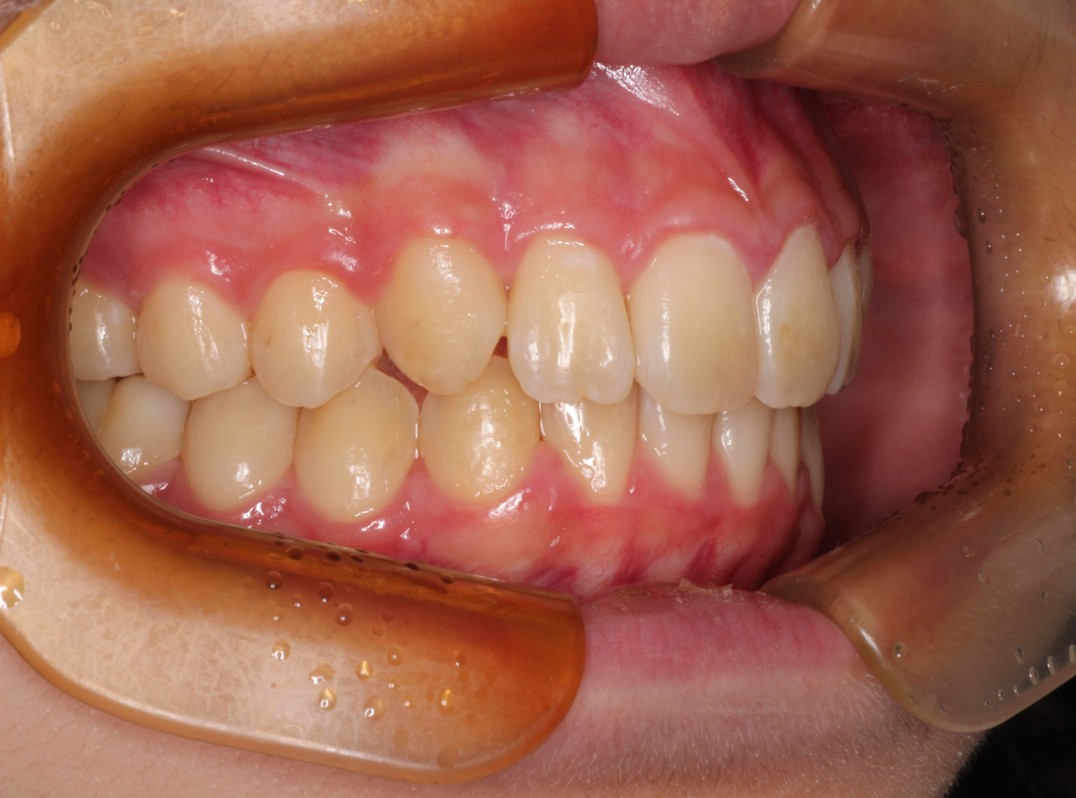

治療前

治療後

出っ歯を治したい。永久歯が生えず不安に思っている。 |

出っ歯と下の永久歯が生えるスペースがないことを主訴にご来院されました。 |

Ⅰ期治療は前歯の歯並びだけを揃えましたが、奥歯の歯並びも綺麗にしたいとのことだったのでⅡ期治療も行いました。 |